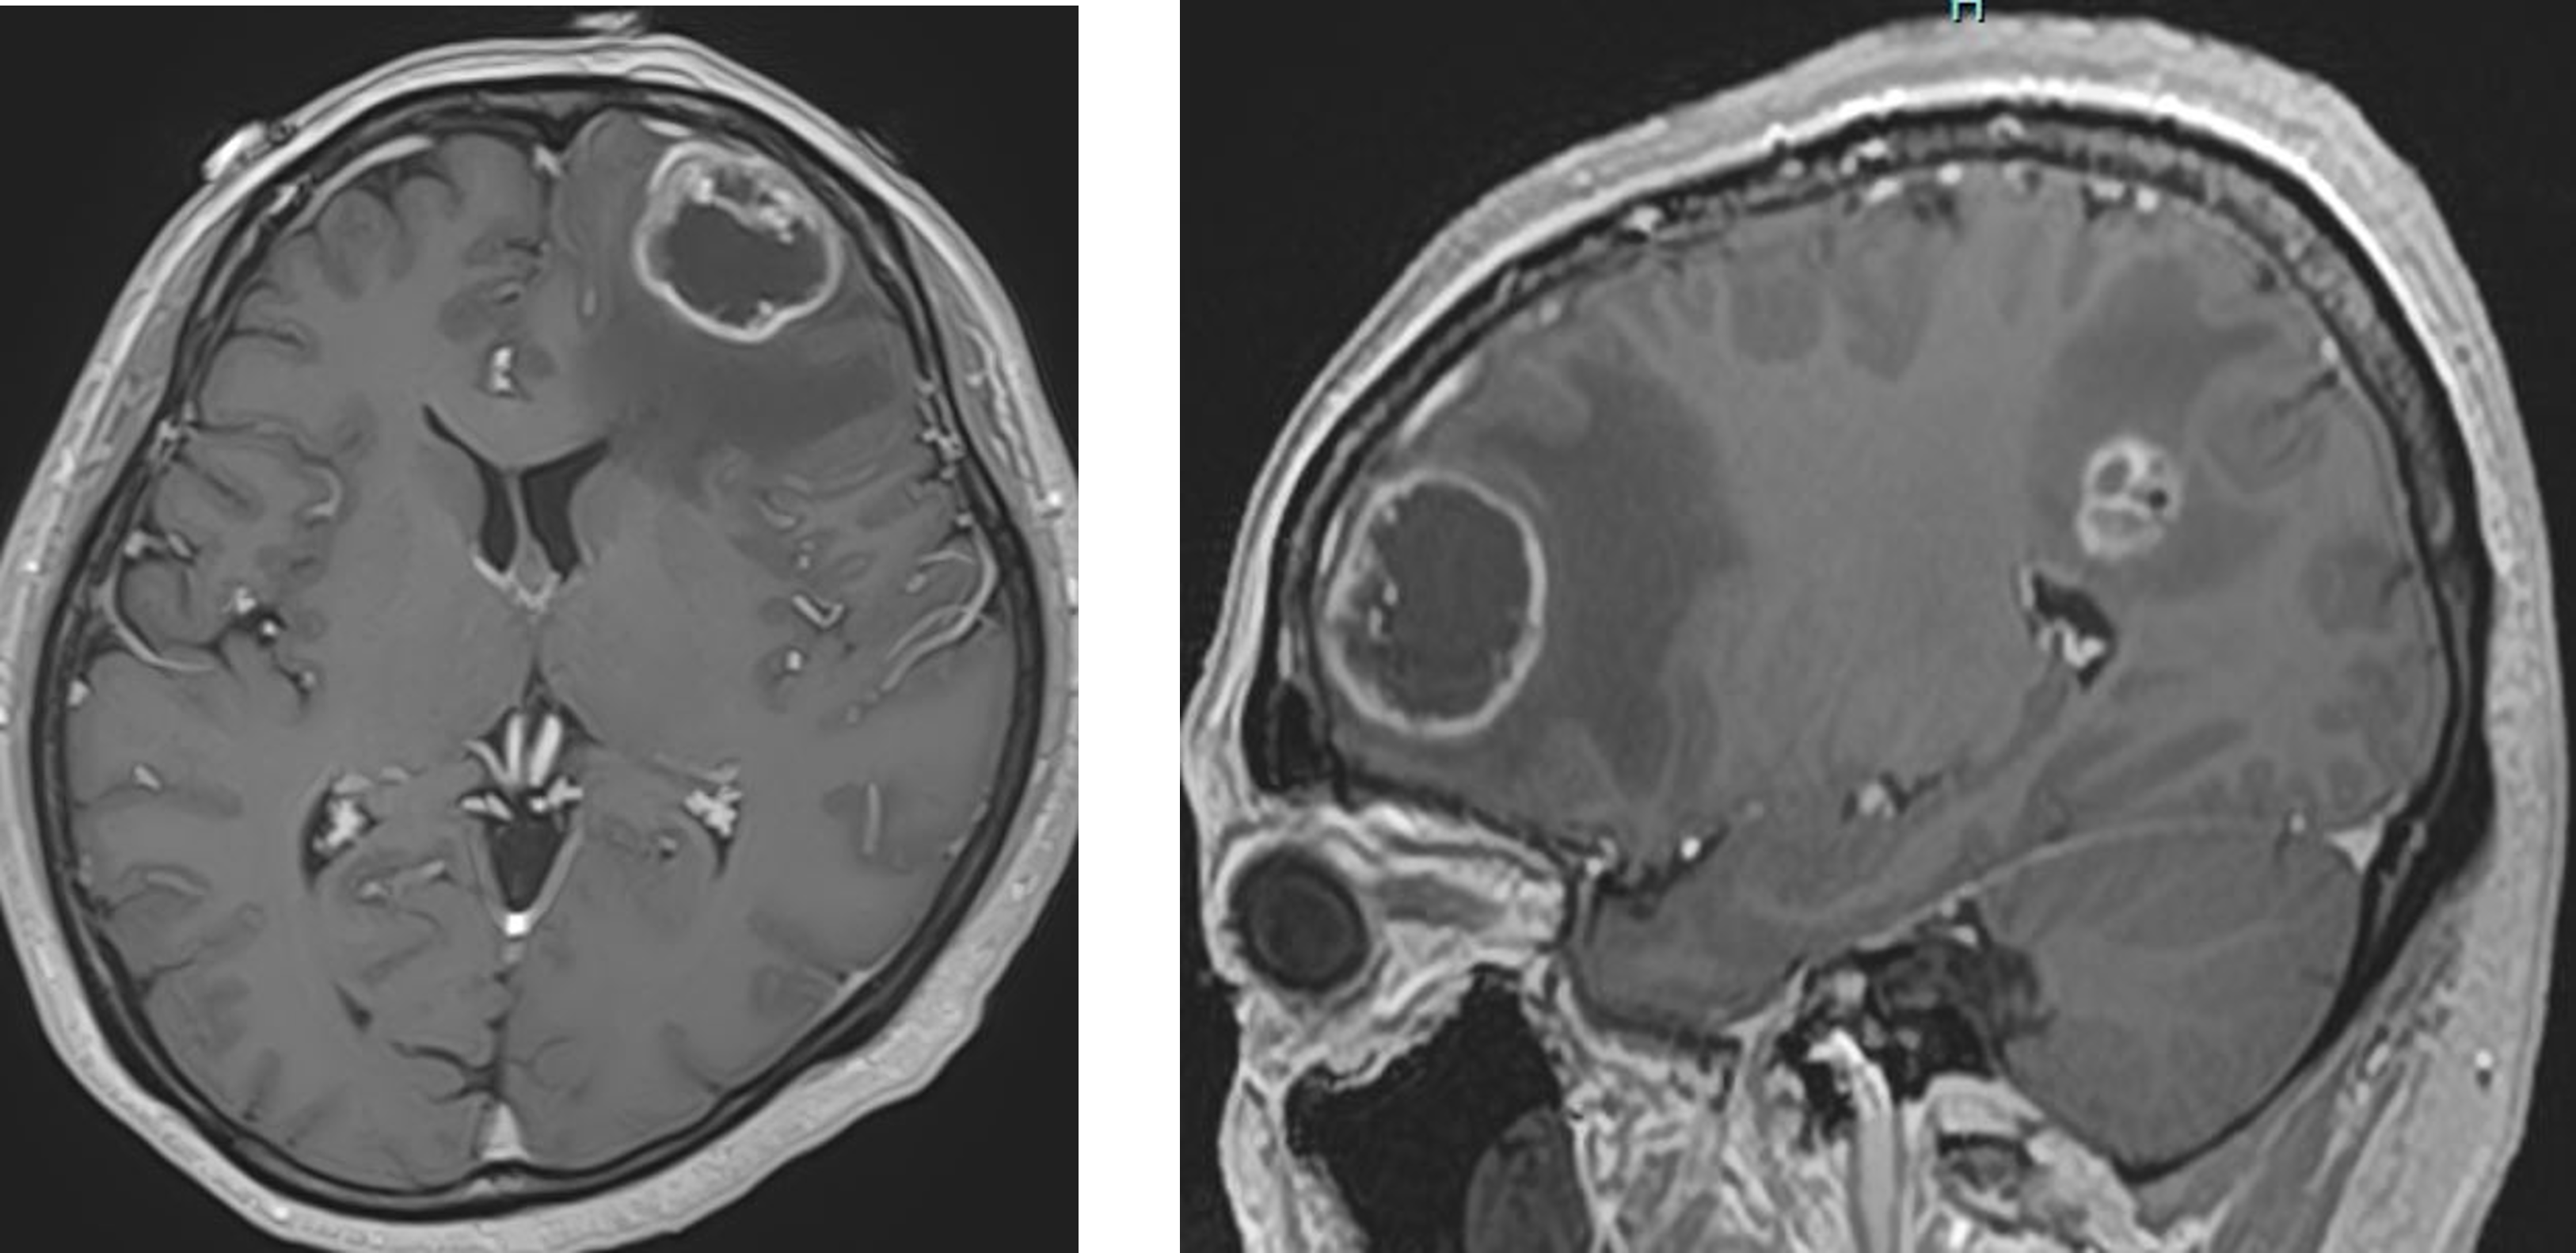

転移性脳腫瘍

転移性脳腫瘍は、頭蓋内以外のがん病巣より、主に血行性転移を起こした疾患です。一般的に、病変や3㎝以上の大きさで、原発巣のコントロールが比較的良く、少なくとも6カ月以上の生存が見込める症例が手術適応となります。手術により局在症状、脳圧亢進症状の改善を図ることにより、日常生活動作を維持したり生活の質(クオリティ・オブ・ライフ)の回復を目指すことで、がん治療を継続できることが目標になります。

それ以外の転移性脳腫瘍は、全脳照射や定位放射線治療(サイバーナイフやガンマナイフ、ライナックナイフなど)といった定位放射線療法が有効な場合があります。転移巣が複数ある場合が多くある場合にも有効な治療法になります。大阪大学やその他、放射線治療可能施設と連携しており、治療を行っております。我々が参加したJCOG0504試験では、複数ある転移巣の場合も、大きいものは腫瘍を摘出し、残りは定位放射線療法する方法は、標準治療である全脳照射と比較して非劣性であったという結果となっております。